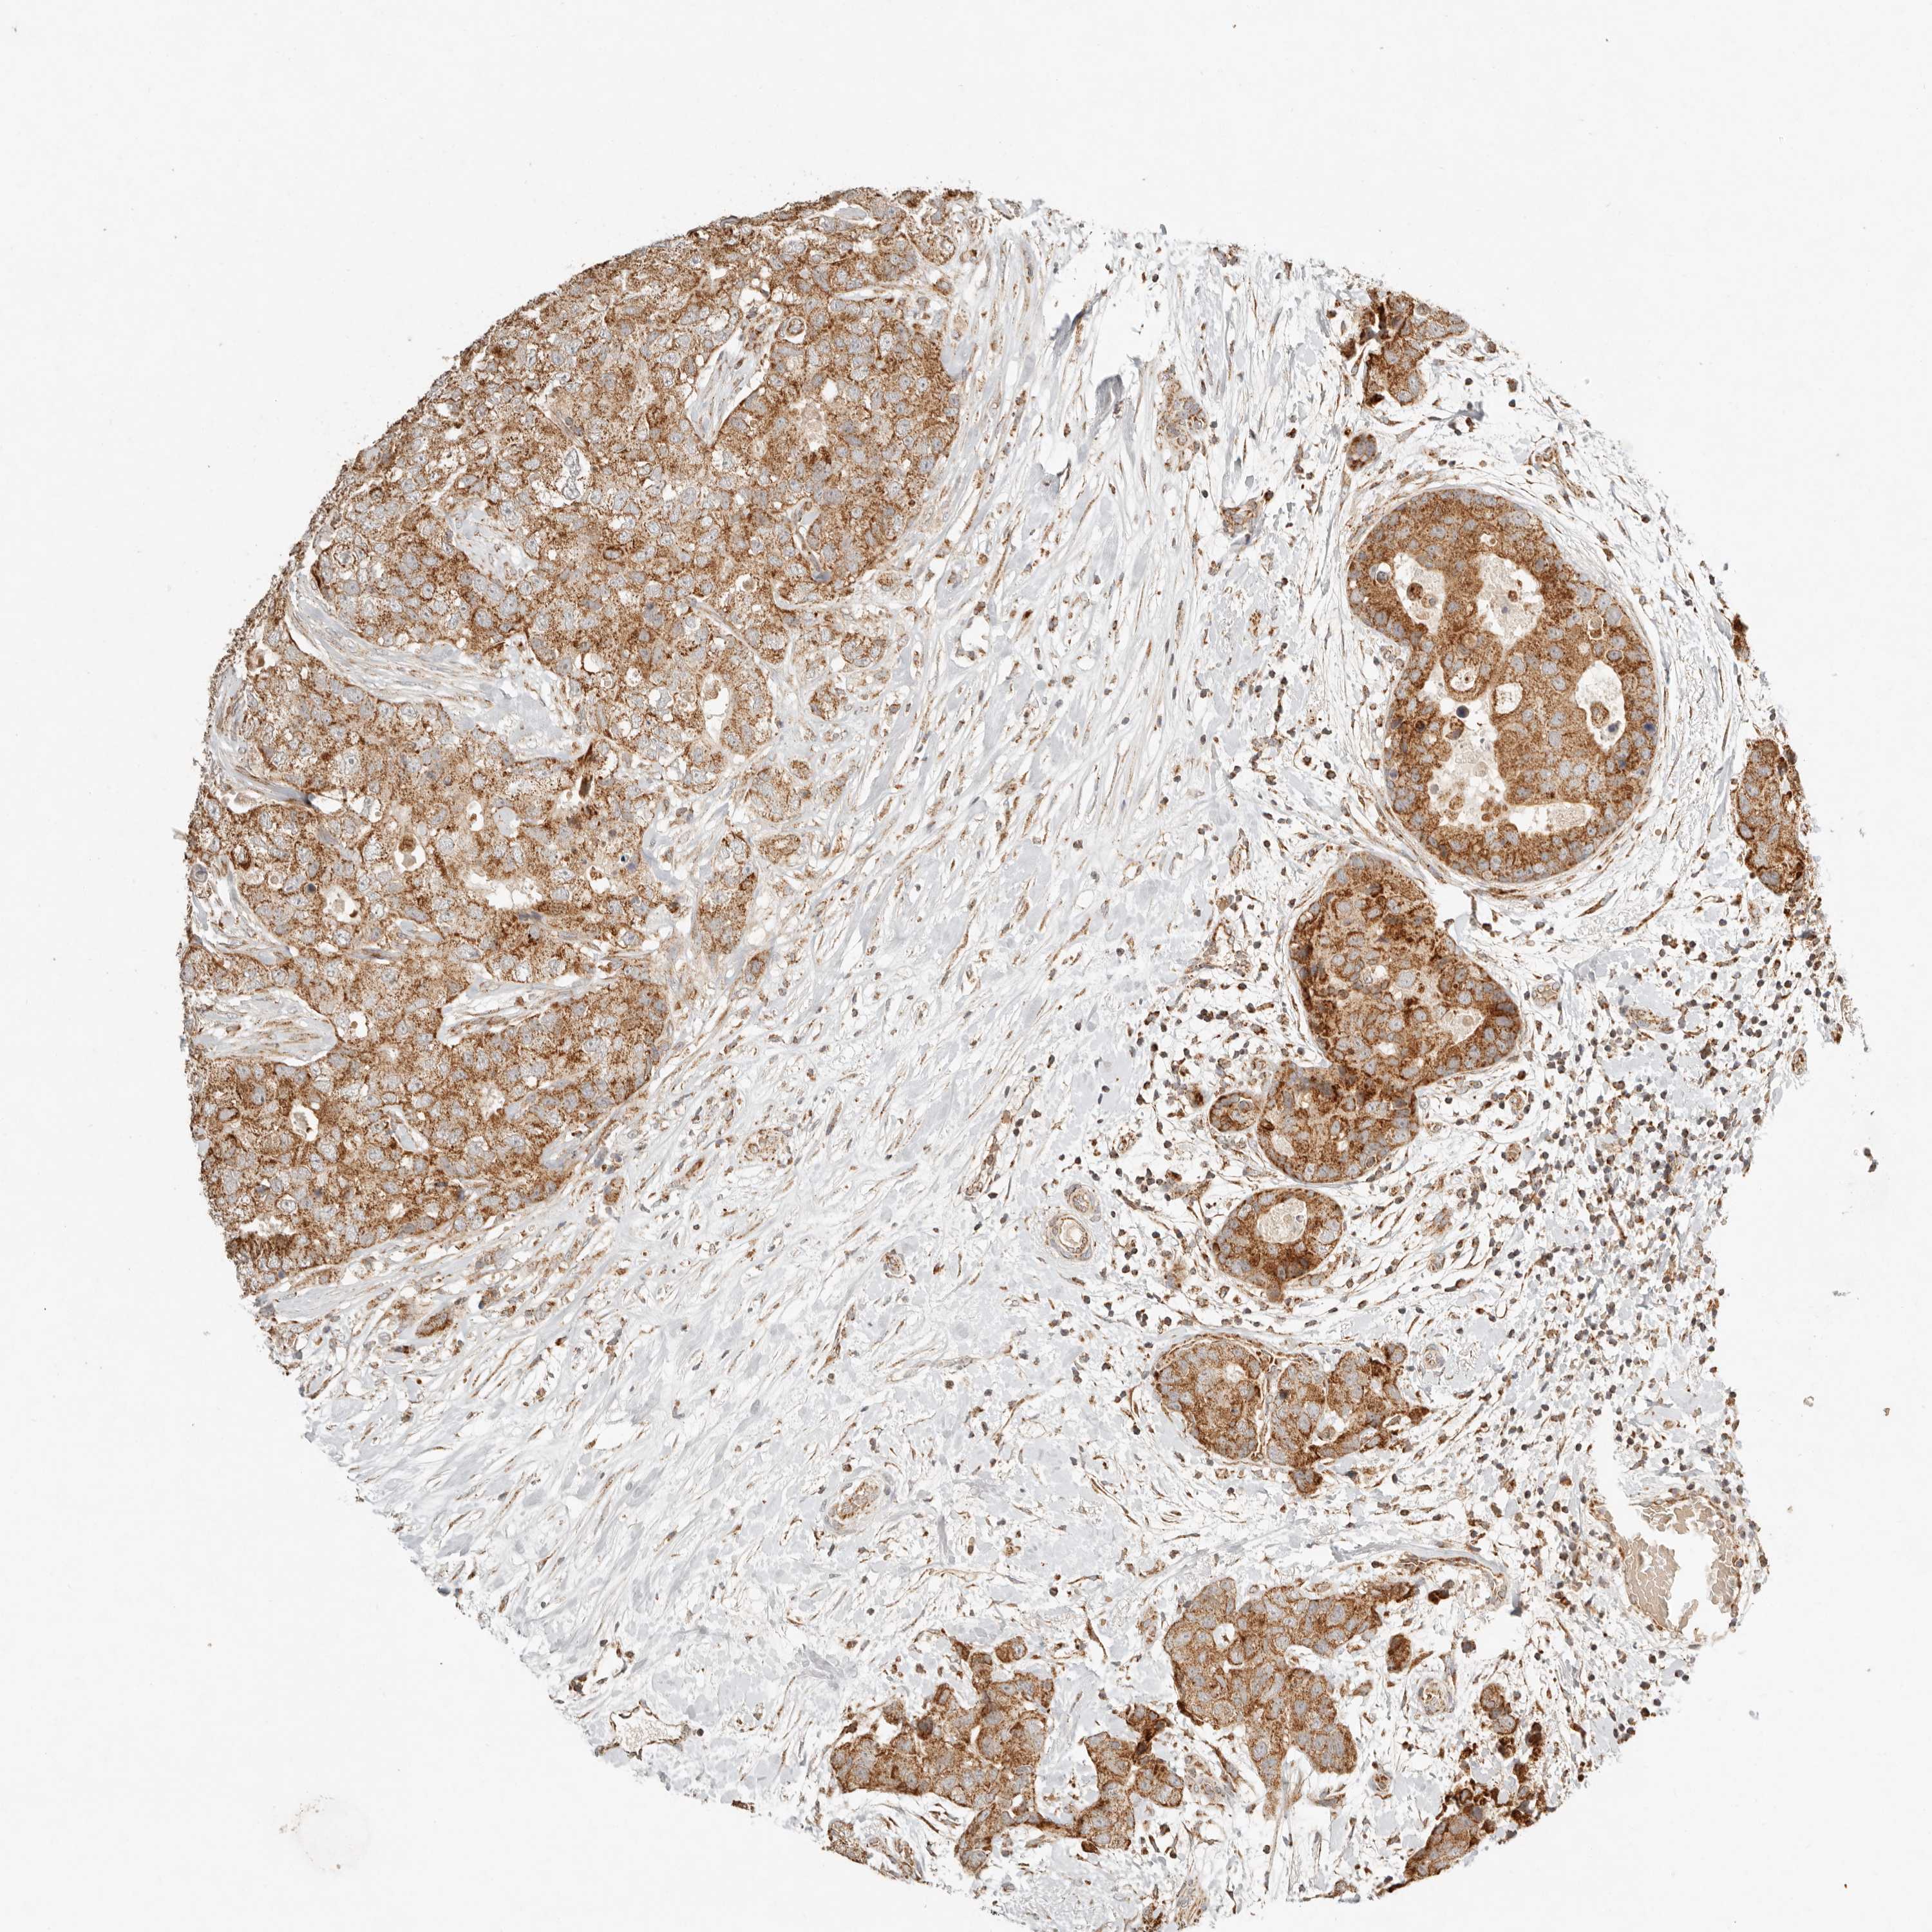

CANCER BREAST CANCER Show tissue menu

BRCA TCGA BRCA VALIDATION PROTEIN EXPRESSION